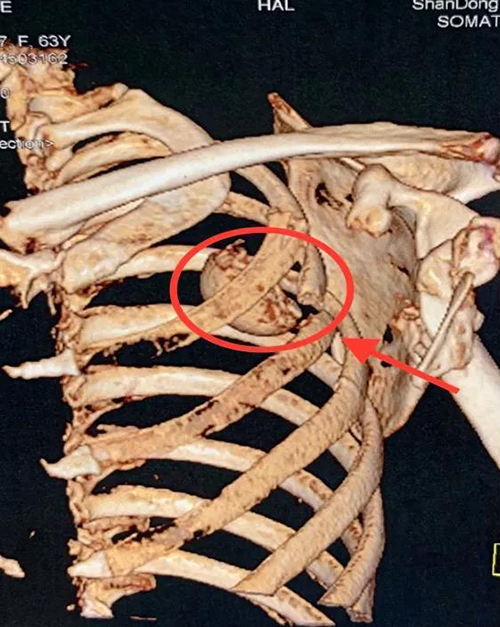

患者马某64岁,车祸伤导致肱骨近端粉碎性骨折。该病例骨折粉碎移位严重,断裂脱位的肱骨头撞断肋骨后进入胸腔,此种损伤极其罕见,经文献检索国内外尚无此类报道。因肩关节内侧密布腋血管及臂丛神经,肱骨头取出困难,稍有不慎便会导致严重并发症,治疗难度及风险都非常大。

手术由创伤一科张琰主任医师主刀,术中探查发现游离的肱骨头经喙突下、腋动脉臂丛神经深面,撞断肋骨后,进入胸腔内。原始创伤通道处大血管神经交织,肺裂伤后创口内较多出血,再加上肋骨阻挡,手术部位很深,操作空间狭窄,稍有不慎便可致腋动脉或其分支大出血,臂丛神经损伤致患者术后上肢活动障碍等严重并发症。在场指导的创伤一科副主任王鲁博与张琰主任医师果断选用备选治疗方案——请胸外科协助开胸探查取出肱骨头。

胸外科王磊主任医师经前胸第三肋间开胸,探查发现肱骨头位于左肺上叶深部,并导致肺部裂伤,徒手取出肱骨头后,对裂伤的肺叶进行了修复,放置胸腔闭式引流。肱骨头取出后,张琰主任医师对严重粉碎的复杂肱骨近端骨折进行了准确的解剖复位及可靠的内固定。手术历时约3小时,术中患者生命体征平稳,术后患者安返病房,病情稳定,术后第四天顺利拔除胸腔闭式引流,恢复良好,顺利出院。

术中取出的肱骨头